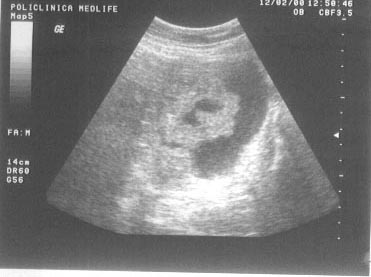

Imaginea mixta

Imaginea mixta, neomogena este generata de alternanta de arii hipo si hiperecogene.

Exemple:

necroza sau hemoragia intratumorala;

abcesul hepatic.

Figura

13. Ovarul st`ng este ]nlocuit de o formaiune complex[, transsonic[ =i

solid[. Partea solid[ ]n proporie de 40%, cu ecostructura hiperecogen[

este dispus[ sub forma de prelungiri papilifere cu contur neregulat =i

prezint[ ]n interior c`teva mici zone transsonice (posibil arii de

necroz[). Aspectul sugereaz[ chistadenocarcinom ovarian.